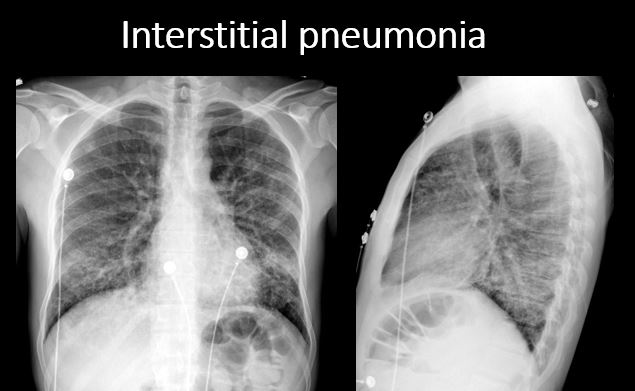

There is focal or diffuse interstitial disease. [Yes/No]